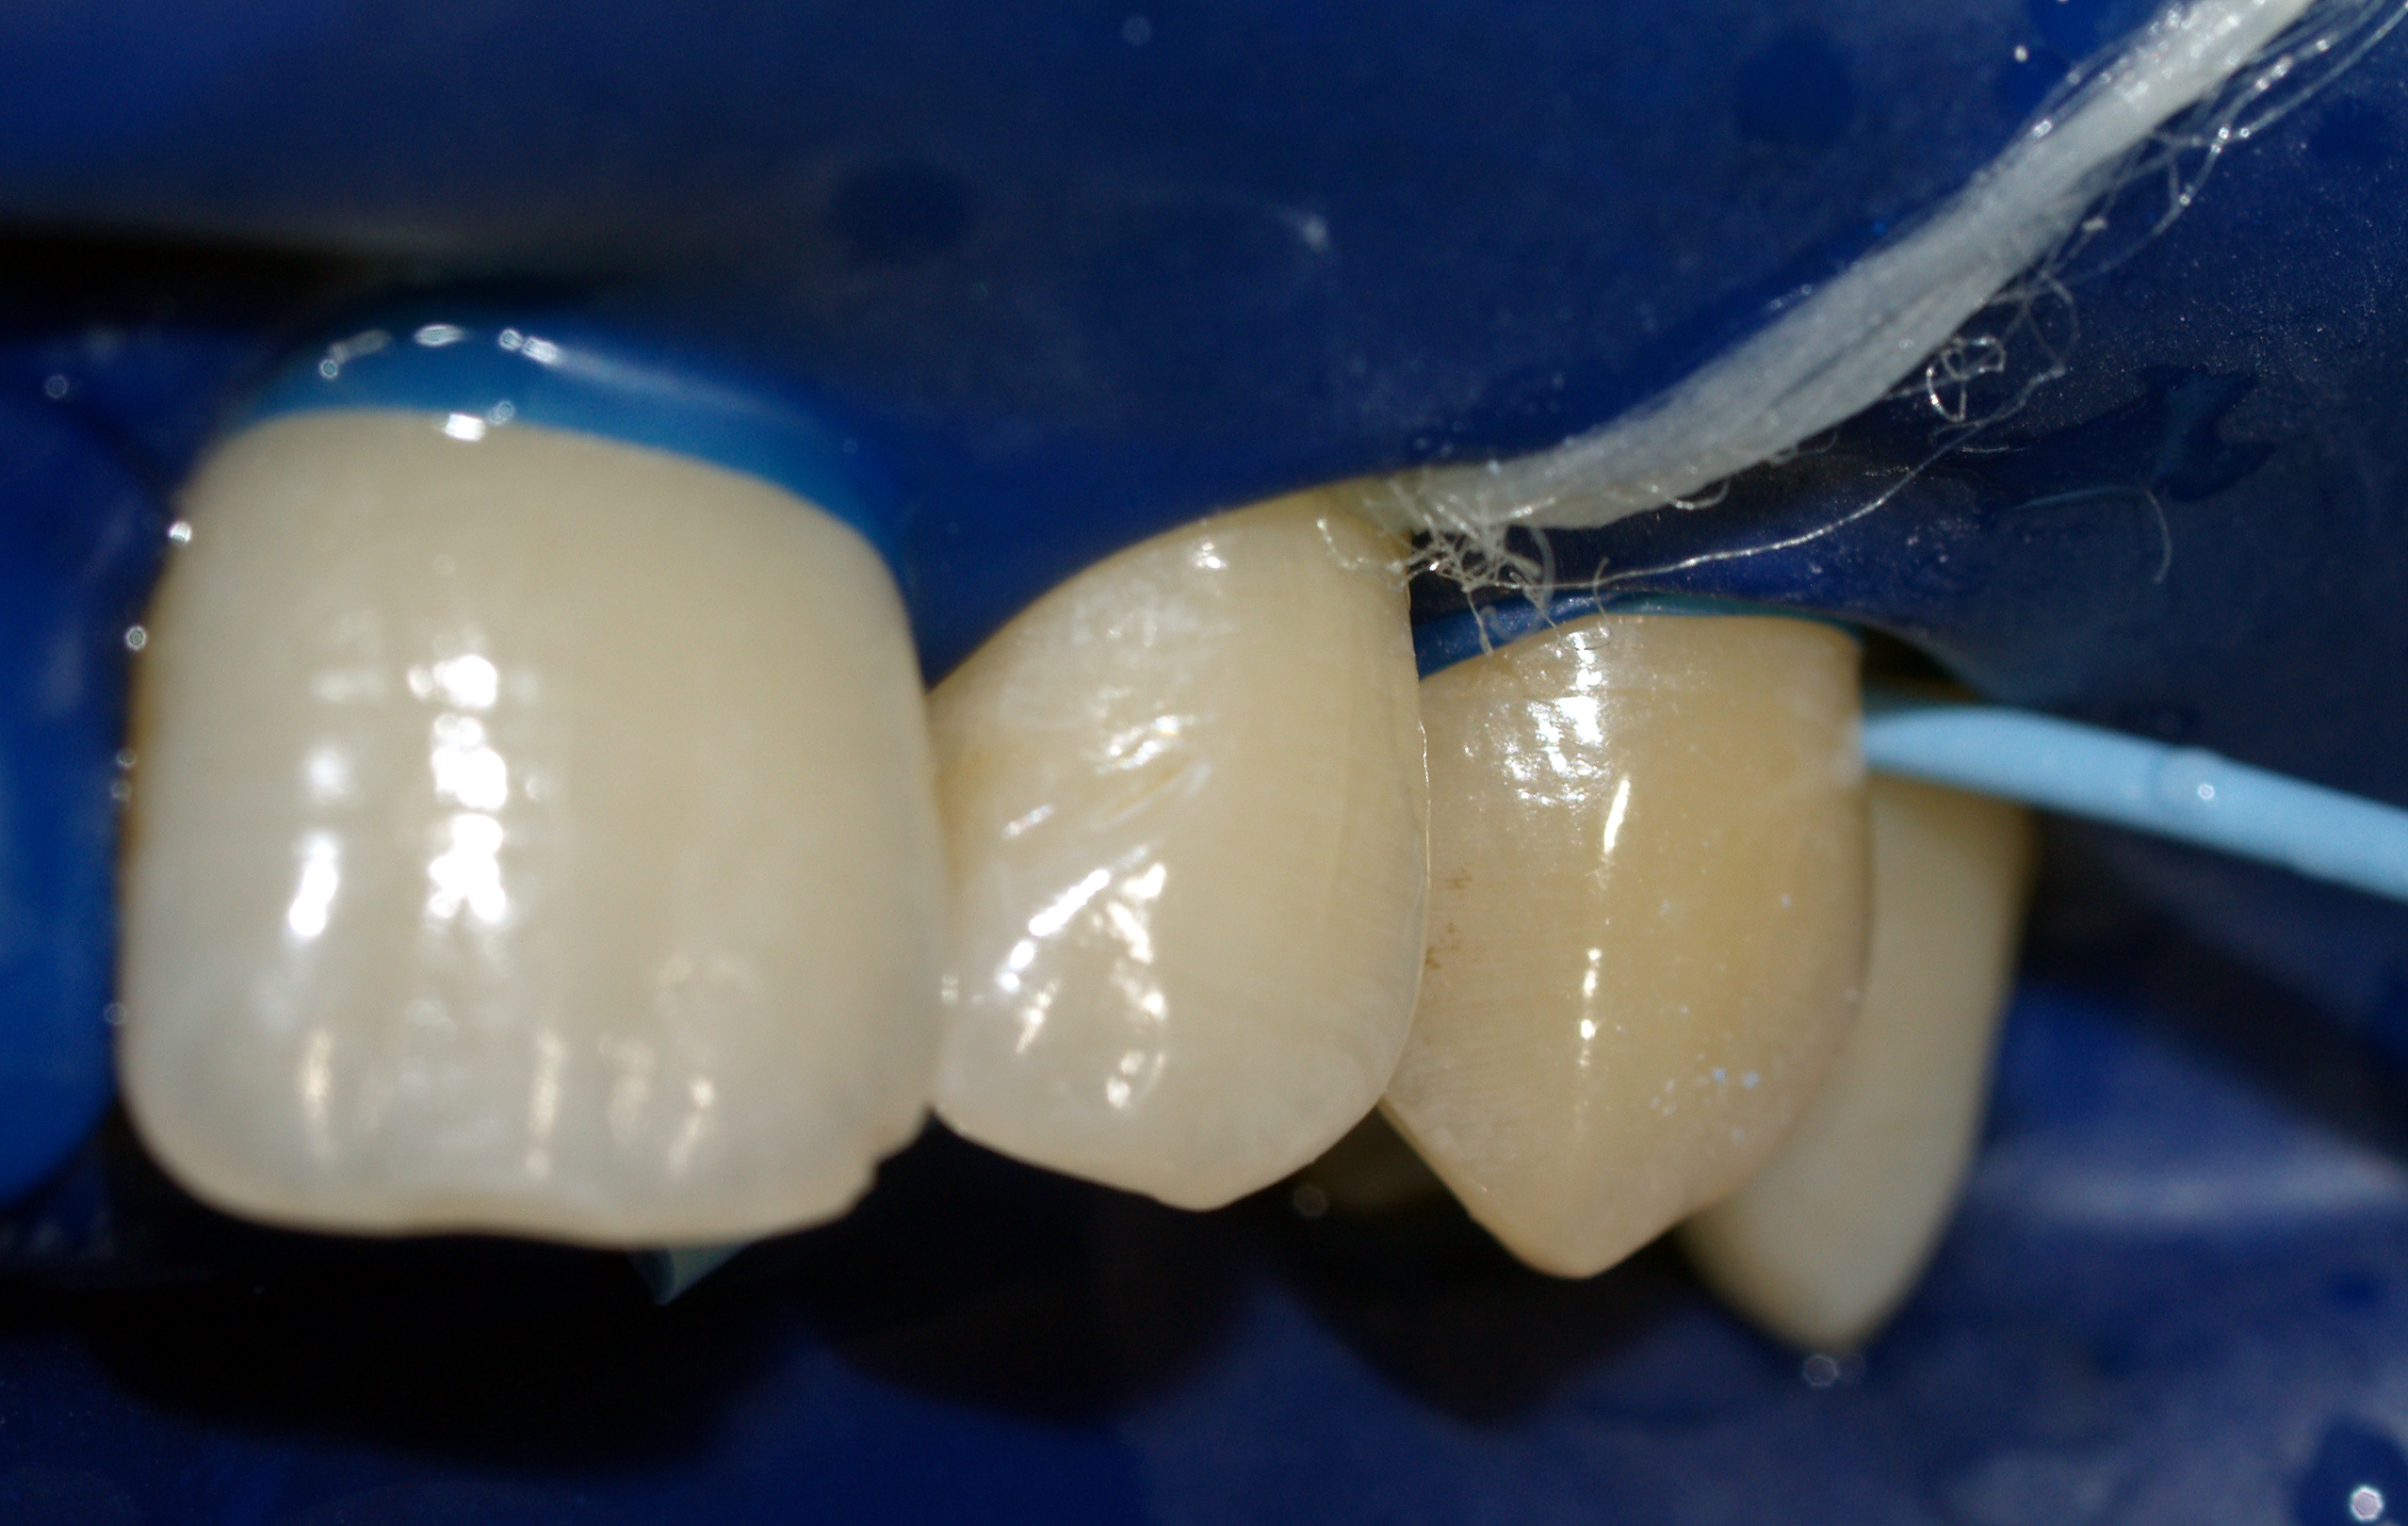

Kategoria: 2.2 Wypełnienia i rekonstrukcje

Niewielkie uszkodzenie szkliwa o nierównej powierzchni sprzyja kumulacji płytki i tworzeniu przebarwień. Po delikatnym wygładzeniu powierzchnię wytrawiono, a następnie odbudowano materiałem złożonym. Pierwotnie nieco jaśniejszy materiał doskonale integruje się z tkankami po starannym wypolerowaniu jego powierzchni.